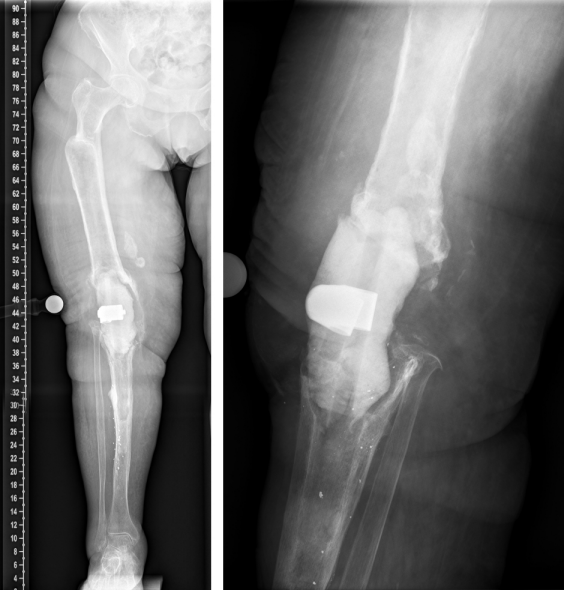

This is a report on a female patient aged 80 years at time of last surgery. The patient was first admitted to our center in 2016. Primary right-sided total knee replacement was carried out in 1994, revision surgery due to aseptic loosening was then performed in 2005. In 2016, aseptic loosening of the components was diagnosed again (Figure 1 [Fig. 1]). Revision surgery was carried out with distal femoral replacement (Figure 2 [Fig. 2]). In 2020, the patient presented to us with insufficiency of the extensor apparatus. According to the clinical picture, especially the macroscopic findings during surgery, infection could not be ruled out. Therefore, explantation of the components was carried out with implantation of a cement spacer. The histological and microbiological findings ruled out infection. Therefore, an intramedullary arthrodesis of the knee was carried out during the same hospital stay (Figure 3 [Fig. 3]). In 2022, the patient again complained of pain and we detected loosening of the femoral component. Despite the fact that no microbes were ever isolated in the right knee, we suspected low grade infection, as loosening occurred within less than 2 years accompanied by local signs of infection (Figure 4 [Fig. 4]). Explantation was carried out with implantation of a cement spacer with intramedullary carbon nails (Figure 5 [Fig. 5]). Yet, the histological and microbiological investigations ruled out infection.

Figure 5: Explantation of the nail was carried out with implantation of cement spacer with intramedullary carbon nails.

Surgery was indicated for the definitive treatment of the right knee joint after multiple previous operations and insufficiency of the extensor system. Infection has never been proved histologically or microbiologically. In the proximal area of the femur, there was a sclerotic zone with threatening fracture (Figure 5 [Fig. 5]). In order to prevent a fracture in this zone, a femoral implant was specially made into which a femoral neck screw could be inserted. To avoid a via falsa, the sclerotic bone was approached both proximally and distally. According to the instructions of the surgeon, preoperative planning was done and a custom-made implant was manufactured and delivered by PETER BREHM GmbH (Weisendorf, Germany) within 6 weeks (Attachment 1 [Att. 1]). A special device was introduced to adjust rotation of the femoral nail prior to its implantation in order to adequately place the femoral neck screw (Attachment 1 [Att. 1]). The surgical procedure was explained to the patient in detail.

We report on this case due to the particular feature of the custom-made arthrodesis nail of the knee with the additional femoral neck screw. The challenging part of this surgery was avoiding via falsa or even fracture of the femoral shaft close to the sclerotic zone (Figure 5 [Fig. 5]). Yet, the major technical challenge was introducing the femoral nail in correct rotation to allow adequate positioning of the femoral neck screw.